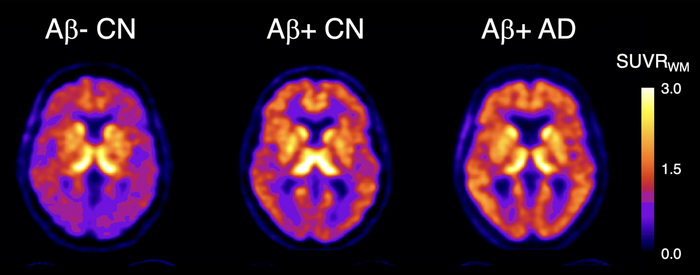

18F-SMBT-1 PET studies showed that beta-amyloid+ Alzheimer’s disease (AD) patients, but most importantly, beta-amyloid+ controls (CN) have significantly higher regional 18F-SMBT-1 binding than beta-amyloid- CN, with 18F-SMBT-1 retention highly associated with beta-amyloid burden. These findings suggest that increased 18F-SMBT-1 binding is detectable at the preclinical stages of beta-amyloid accumulation. Image created by Victor Villemagne, MD, Professor of Psychiatry at the University of Pittsburgh.